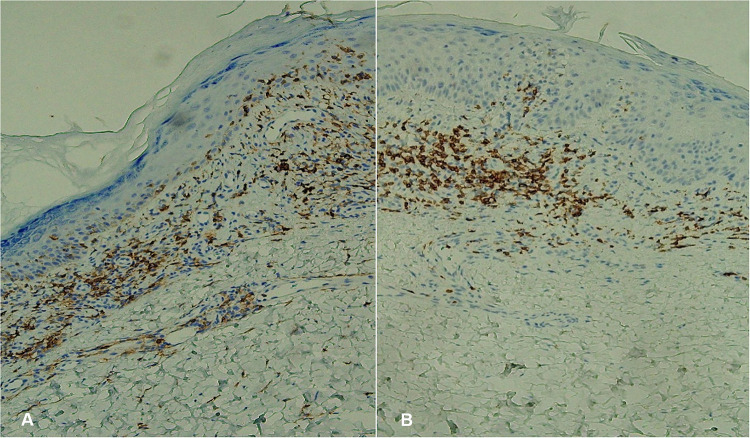

Lichen planus pigmentosus (LPP) and hyperpigmented mycosis fungoides (MF) represent two distinct rare cutaneous disorders. This case explores the potential association between LPP and hyperpigmented MF, a previously unreported progression. The authors report a 52-year-old male presenting with purplish-red macules on the abdomen and upper extremities subsequent to exposure to petrochemicals, initially diagnosed in 2007 with lichen planus (LP). In 2019, LPP was confirmed by histopathological evaluation of a skin biopsy obtained from an outside institution. Despite treatment with hydroxychloroquine sulfate tablets, the lesions exhibited disease progression. After 17 years, generalized hyperpigmentation gradually developed. Repeat biopsies and immunohistochemistry were performed in 2024, leading to the definitive diagnosis of hyperpigmented MF. The patient is currently managed with subcutaneous interferon alpha-2b (IFNα-2b) injections, with the rash color showing slight lightening. In conclusion, the cutaneous manifestations of MF demonstrate marked heterogeneity, requiring systematic clinical evaluation and histopathological assessment to facilitate accurate diagnosis and guide the development of stage-appropriate treatment protocols. Whether the transformation from LPP to hyperpigmented MF is rare, impossible, or a missed diagnosis remains to be further clarified with more reported cases.